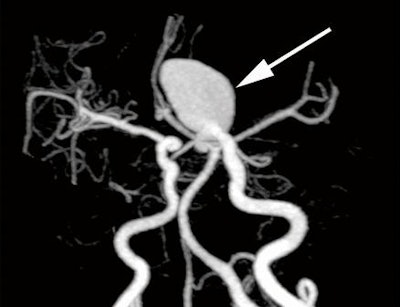

As a result, the group sought to determine if subtracted 320-detector-row volumetric CTA, which offers bone-free visualization of aneurysms, could accurately detect cerebral aneurysms.

The subtracted CTA volumetric data were gathered by subtracting the mask image volumetric data from the conventional nonsubtracted CTA volumetric data using the console's software. Bone-tissue data were automatically removed, and the resulting data were reviewed on a Voxar workstation (Toshiba) for 3D visualization using direct volume-rendering techniques or maximum-intensity projections.

"The accuracy of nonsubtracted volumetric CT angiography was lower than that for subtracted volumetric CT angiography, especially for aneurysms adjacent to bone tissue," the authors wrote.

"The aneurysms missed at nonsubtracted volumetric CT angiography were generally located in the internal carotid artery," they wrote. "Detection of cerebral aneurysms adjacent to bone tissue was still challenging at nonsubtracted volumetric CT angiography because of the presence of overlying bone structures."

Subtracted volumetric CTA also had its limitations: The two missed cerebral aneurysms on subtracted volumetric CTA were microaneurysms, which the technique generally struggled to identify. The technique also does not display atherosclerotic plaque and aneurysmal calcification, and it could not present the relationship of aneurysms to bone structures, according to the group.